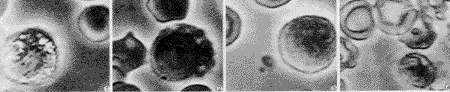

图1~4 左心辅助循环和体外循环前、后血细胞布氏显微镜照片(×8 000) 图1 左心辅助循环前红细胞、白细胞形态正常,白细胞无活化 图2 左心辅助循环后红细胞、白细胞形态正常,白细胞无活化 图3 体外循环前红细胞、白细胞形态正常,白细胞无活化 图4 体外循环后红细胞畸形,白细胞活化